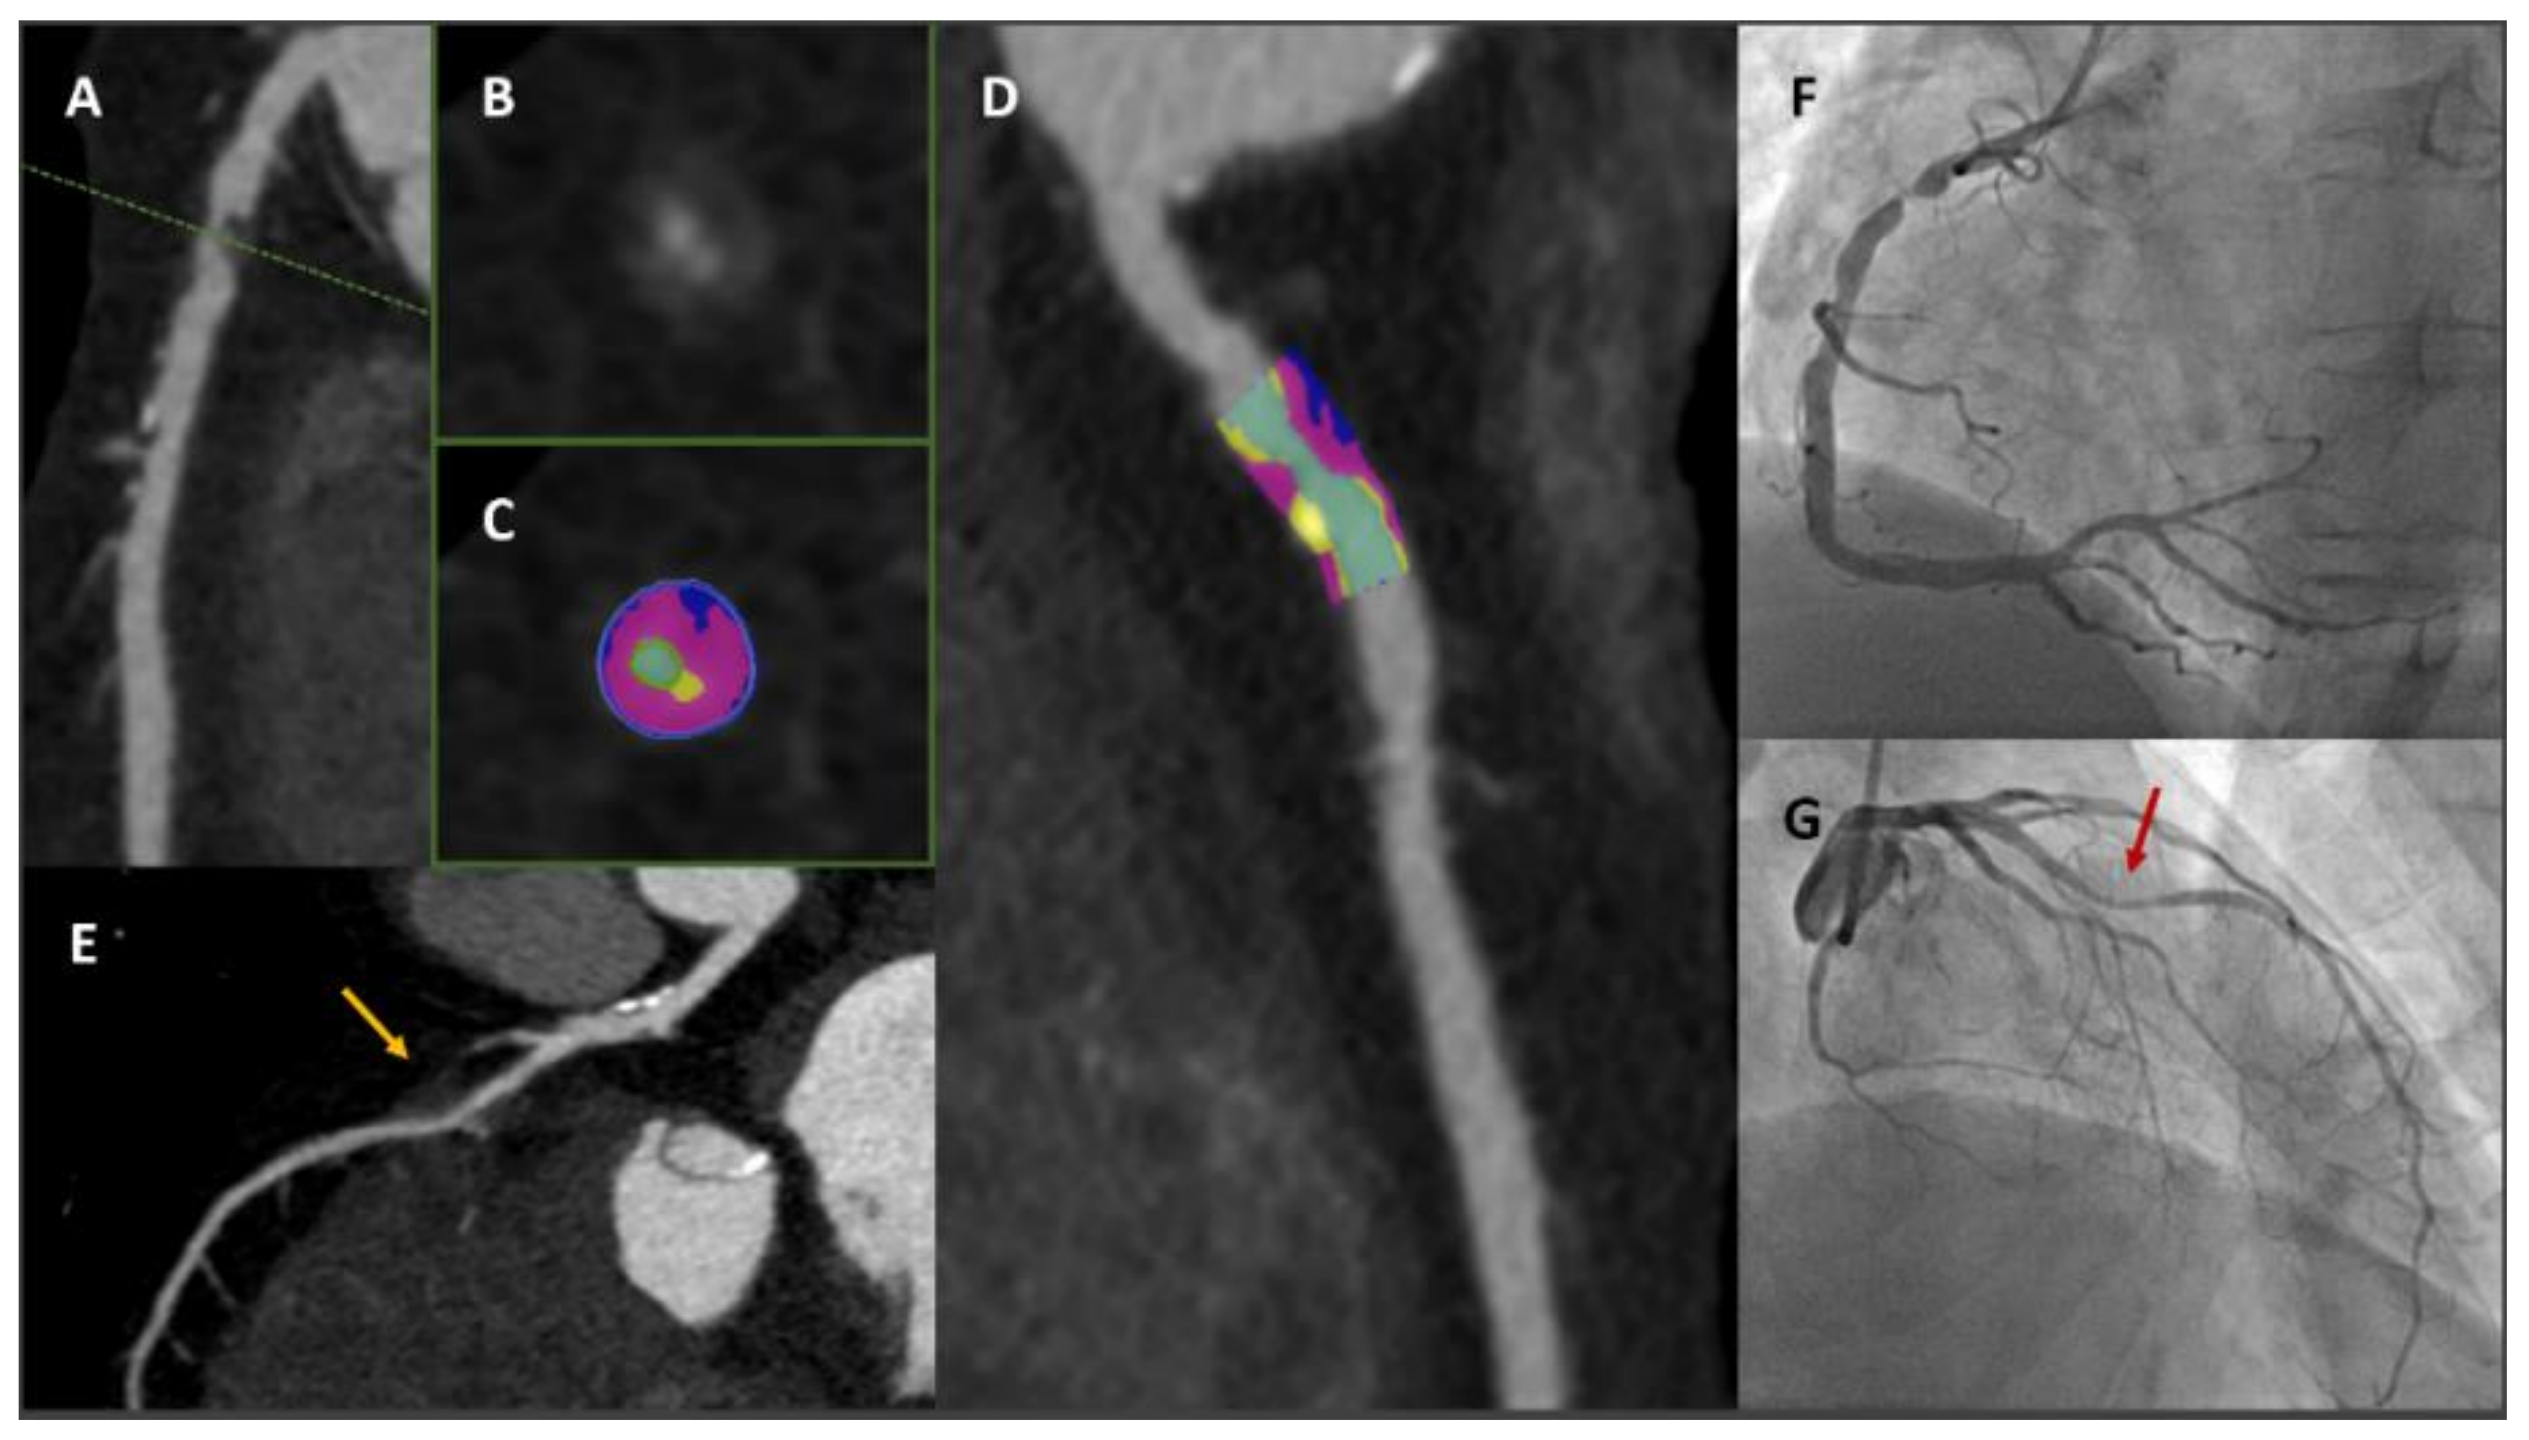

- Pontone, G.; Muscogiuri, G.; Andreini, D.; Guaricci, A.I.; Guglielmo, M.; Mushtaq, S.; Baggiano, A.; Conte, E.; Beltrama, V.; Annoni, A.; et al. The New Frontier of Cardiac Computed Tomography Angiography: Fractional Flow Reserve and Stress Myocardial Perfusion. Curr. Treat. Options Cardiovasc. Med. 2016, 18, 74. [Google Scholar] [CrossRef] [PubMed]

- Pontone, G.; Baggiano, A.; Andreini, D.; Guaricci, A.I.; Guglielmo, M.; Muscogiuri, G.; Fusini, L.; Soldi, M.; Del Torto, A.; Mushtaq, S.; et al. Diagnostic accuracy of simultaneous evaluation of coronary arteries and myocardial perfusion with single stress cardiac computed tomography acquisition compared to invasive coronary angiography plus invasive fractional flow reserve. Int. J. Cardiol. 2018, 273, 263–268. [Google Scholar] [CrossRef]

- Pontone, G.; Baggiano, A.; Andreini, D.; Guaricci, A.I.; Guglielmo, M.; Muscogiuri, G.; Fusini, L.; Soldi, M.; Del Torto, A.; Mushtaq, S.; et al. Dynamic Stress Computed Tomography Perfusion With a Whole-Heart Coverage Scanner in Addition to Coronary Computed Tomography Angiography and Fractional Flow Reserve Computed Tomography Derived. JACC Cardiovasc. Imaging 2019, 12, 2460–2471. [Google Scholar] [CrossRef]

- Baggiano, A.; Fusini, L.; Del Torto, A.; Vivona, P.; Guglielmo, M.; Muscogiuri, G.; Soldi, M.; Martini, C.; Fraschini, E.; Rabbat, M.G.; et al. Sequential Strategy Including FFRCT Plus Stress-CTP Impacts on Management of Patients with Stable Chest Pain: The Stress-CTP RIPCORD Study. J. Clin. Med. 2020, 9, 2147. [Google Scholar] [CrossRef]